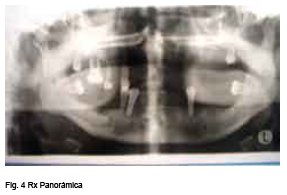

<body><![CDATA[<P align="center"><a name="f2"></a><img src="/img/revistas/chc/v52n2/fig_10_2.jpg" width="284" height="233"><font size="2" face="Verdana, Arial, Helvetica, sans-serif"> </font></P>     <P align="center"><a name="f3"></a><img src="/img/revistas/chc/v52n2/fig_10_3.jpg" width="288" height="195"></P> <font face="Verdana, Arial, Helvetica, sans-serif"></font>    <P align="justify"><font size="2" face="Verdana, Arial, Helvetica, sans-serif"> La paciente es valorada en nuestra Unidad y se solicita ex&aacute;menes complementarios presumiendo diagn&oacute;stico de Fibromatosis gingival cr&oacute;nica Idiop&aacute;tica recidivante; contaba con estudio histopatol&oacute;gico reportando: </font></P>     <P align="center"><font face="Verdana, Arial, Helvetica, sans-serif" align="justify"><font size="2">&quot;Fibromas por irritaci&oacute;n&quot;, </font></font></P> <font face="Verdana, Arial, Helvetica, sans-serif"> </font>     <P align="justify"><font size="2" face="Verdana, Arial, Helvetica, sans-serif"> Adem&aacute;s de Ortopantomograf&iacute;a con el siguiente informe:</font></P> <ul>       <li>     <font size="2" face="Verdana, Arial, Helvetica, sans-serif" align="justify">Maxilar superior: reabsorci&oacute;n &oacute;sea marginal marcada con remanente &oacute;seo, oste&iacute;tis de furca pieza 16, atrofia &oacute;sea marcada en regi&oacute;n anterosuperior. Maxilar inferior: reabsorci&oacute;n &oacute;sea marginal aplanamiento de la superficie articular de condilo derecho. </font></li>     </ul> <font face="Verdana, Arial, Helvetica, sans-serif">     <P align="center"><a name="f4"></a><img src="/img/revistas/chc/v52n2/fig_10_4.jpg" width="287" height="195"><font size="2"> </font></P> </font>     <P align="justify"><font size="2" face="Verdana, Arial, Helvetica, sans-serif"> Con los resultados de ex&aacute;menes solicitados se decide su internaci&oacute;n para tratamiento quir&uacute;rgico. Por otro lado se solicita estudio hormonal: impresionando TSH 0.09 UI/ml(<img src="/img/revistas/chc/v52n2/arrow.gif" width="7" height="13">)</font></P> <font face="Verdana, Arial, Helvetica, sans-serif">     <P align="justify"><font size="2">Luego de lo anterior se realiza biopsia excisional bajo </font><font size="2">anestesia general, evidenci&aacute;ndose tejido fibroso, </font><font size="2">muy vascularizado, con aparente compromiso de tejido &oacute;seo alveolar superior de lado derecho. En su postoperatorio inmediato paciente recibe transfusi&oacute;n sangu&iacute;nea de un paquete globular, debido a sangrado transoperatorio importante. (<a href="#f5">Fig. 5</a>) </font></P>     ]]></body>